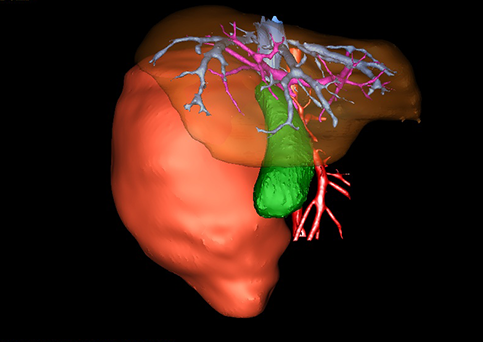

近年来由于数字医学的发展,基于可视化三维重建技术的计算机辅助手术系统极大推进了小儿肝脏肿瘤的精准手术的进步。可以立体透视肝脏解剖、精确掌握肝段的边界、精确测算肝段乃至任意血管所支配的功能体积、准确定位病灶及其与邻近血管的解剖关系,最终对不同手术方案进行比较、筛选和优化。因此,计算机辅助手术规划系统是实现精准肝切除的有力辅助工具,是未来数字外科、精准外科等21世纪外科新理念的重要技术支撑。

计算机辅助手术规划系统具有良好的操作可行性、计算准确性和三维显示效果,可半透明、交互式显示真实的肝内立体解剖关系和空间管道变异,准确计算肝内管道的直径、走行角度,两点间的垂直距离,和任意血管的支配或引流范围等传统二维影像无法获取的信息,有助于实施个体化手术,提高了手术的确定性、预见性和可控性。计算机辅助手术规划系统可直观显示预留肝脏的结构和功能,并可通过虚拟切割功能辅助术者对手术方案进行蹄选和优化,系统评估手术风险和制定对策,改变了部分二维规划的术式和切除范围,使部分二维规划认为不能切除的患者成功手术,提高了手术的根治性、安全性和病变的可切除性,更加符合精准肝脏外科的术前规划要求。详见第11章。

随着计算机技术及影像检查技术的不断发展,以精确的术前影像学和功能评估、精细的手术操作为核心的精准肝切除技术日益受到重视。基于数字医学的计算机辅助手术技术(computer-assisted surgery,CAS)则是实现肝脏精准手术操作的基础。计算机辅助手术系统(CAS)可将术前二维(two dimensional,2D)的CT/MRI影像数据进行三维(three dimensional,3D)重建,建立个体化的肝脏三维解剖模型,清晰显示肝脏内脉管系统的走行及解剖关系,还原病灶与其周围脉管结构的立体解剖构象,准确地对病变进行定位、定性和评估,制定合理、定量的手术方案,实施个体化的肝脏血管取舍分配方案及实施精准肝脏手术。一般认为CAS包括:创建虚拟的患者的图像;患者图像的分析与深度处理;诊断、手术前规划、手术步骤的模拟;术中实时导航。应用本技术后,由于可以更清晰地看出肿瘤的界限,特别是根据肝血管的显影,判断出肿瘤与门静脉及肝静脉的关系以在手术前较准确地估计出手术成功切除的可行性。以往部分根据普通强化CT判断无法手术的病例而被评估为可以成功切除并手术成功。